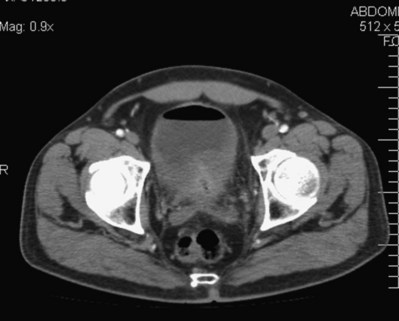

In addition to contrast cystography and VCUG, CT, ultrasonography, and magnetic resonance imaging (MRI) have been used in the evaluation of VVF (Kuhlman and Fishman, 1990; Outwater and Schiebler, 1993; Yang et al, 1994). Delayed CT visualization of contrast within the vagina is considered highly suspicious for VVF in the majority of cases (Kuhlman and Fishman, 1990) (Fig. 77–10). In cases of suspected VVF, CT should be performed with only intravenous contrast, or, alternatively, a CT cystogram can be performed to isolate the bladder. A vaginal tampon placed per vagina during IVU or CT scan may improve the sensitivity for finding small or occult VVF in patients with an otherwise negative evaluation (Wesolowski and Meaney, 1977). Cross-sectional imaging may also be helpful in assessing for recurrent malignant disease in those with such a history.

Figure 77–10 CT scan of vesicovaginal fistula (VVF). A, After intravenous administration of the contrast agent, there is high-density material in both the bladder and vagina consistent with a VVF. The fistulous connection between the bladder anteriorly and the vagina posteriorly. B, Sagittal CT reconstruction demonstrating VVF.